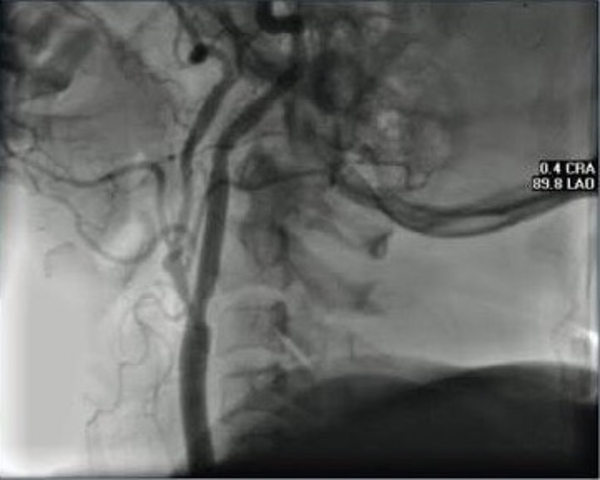

• Primer cirugía de arteria carótida exitosa.

Primer cirugía de arteria carótida exitosa.

Realizada por el doctor Feliz Eastcott, bajo la supervisión del Dr. Rob, fue realizada a una mujer de 66 años con ceguera en el ojo izquierdo y parálisis del lado contrario del cuerpo. Fue tan exitosa que estos síntomas desaparecieron después del periodo de recuperación.